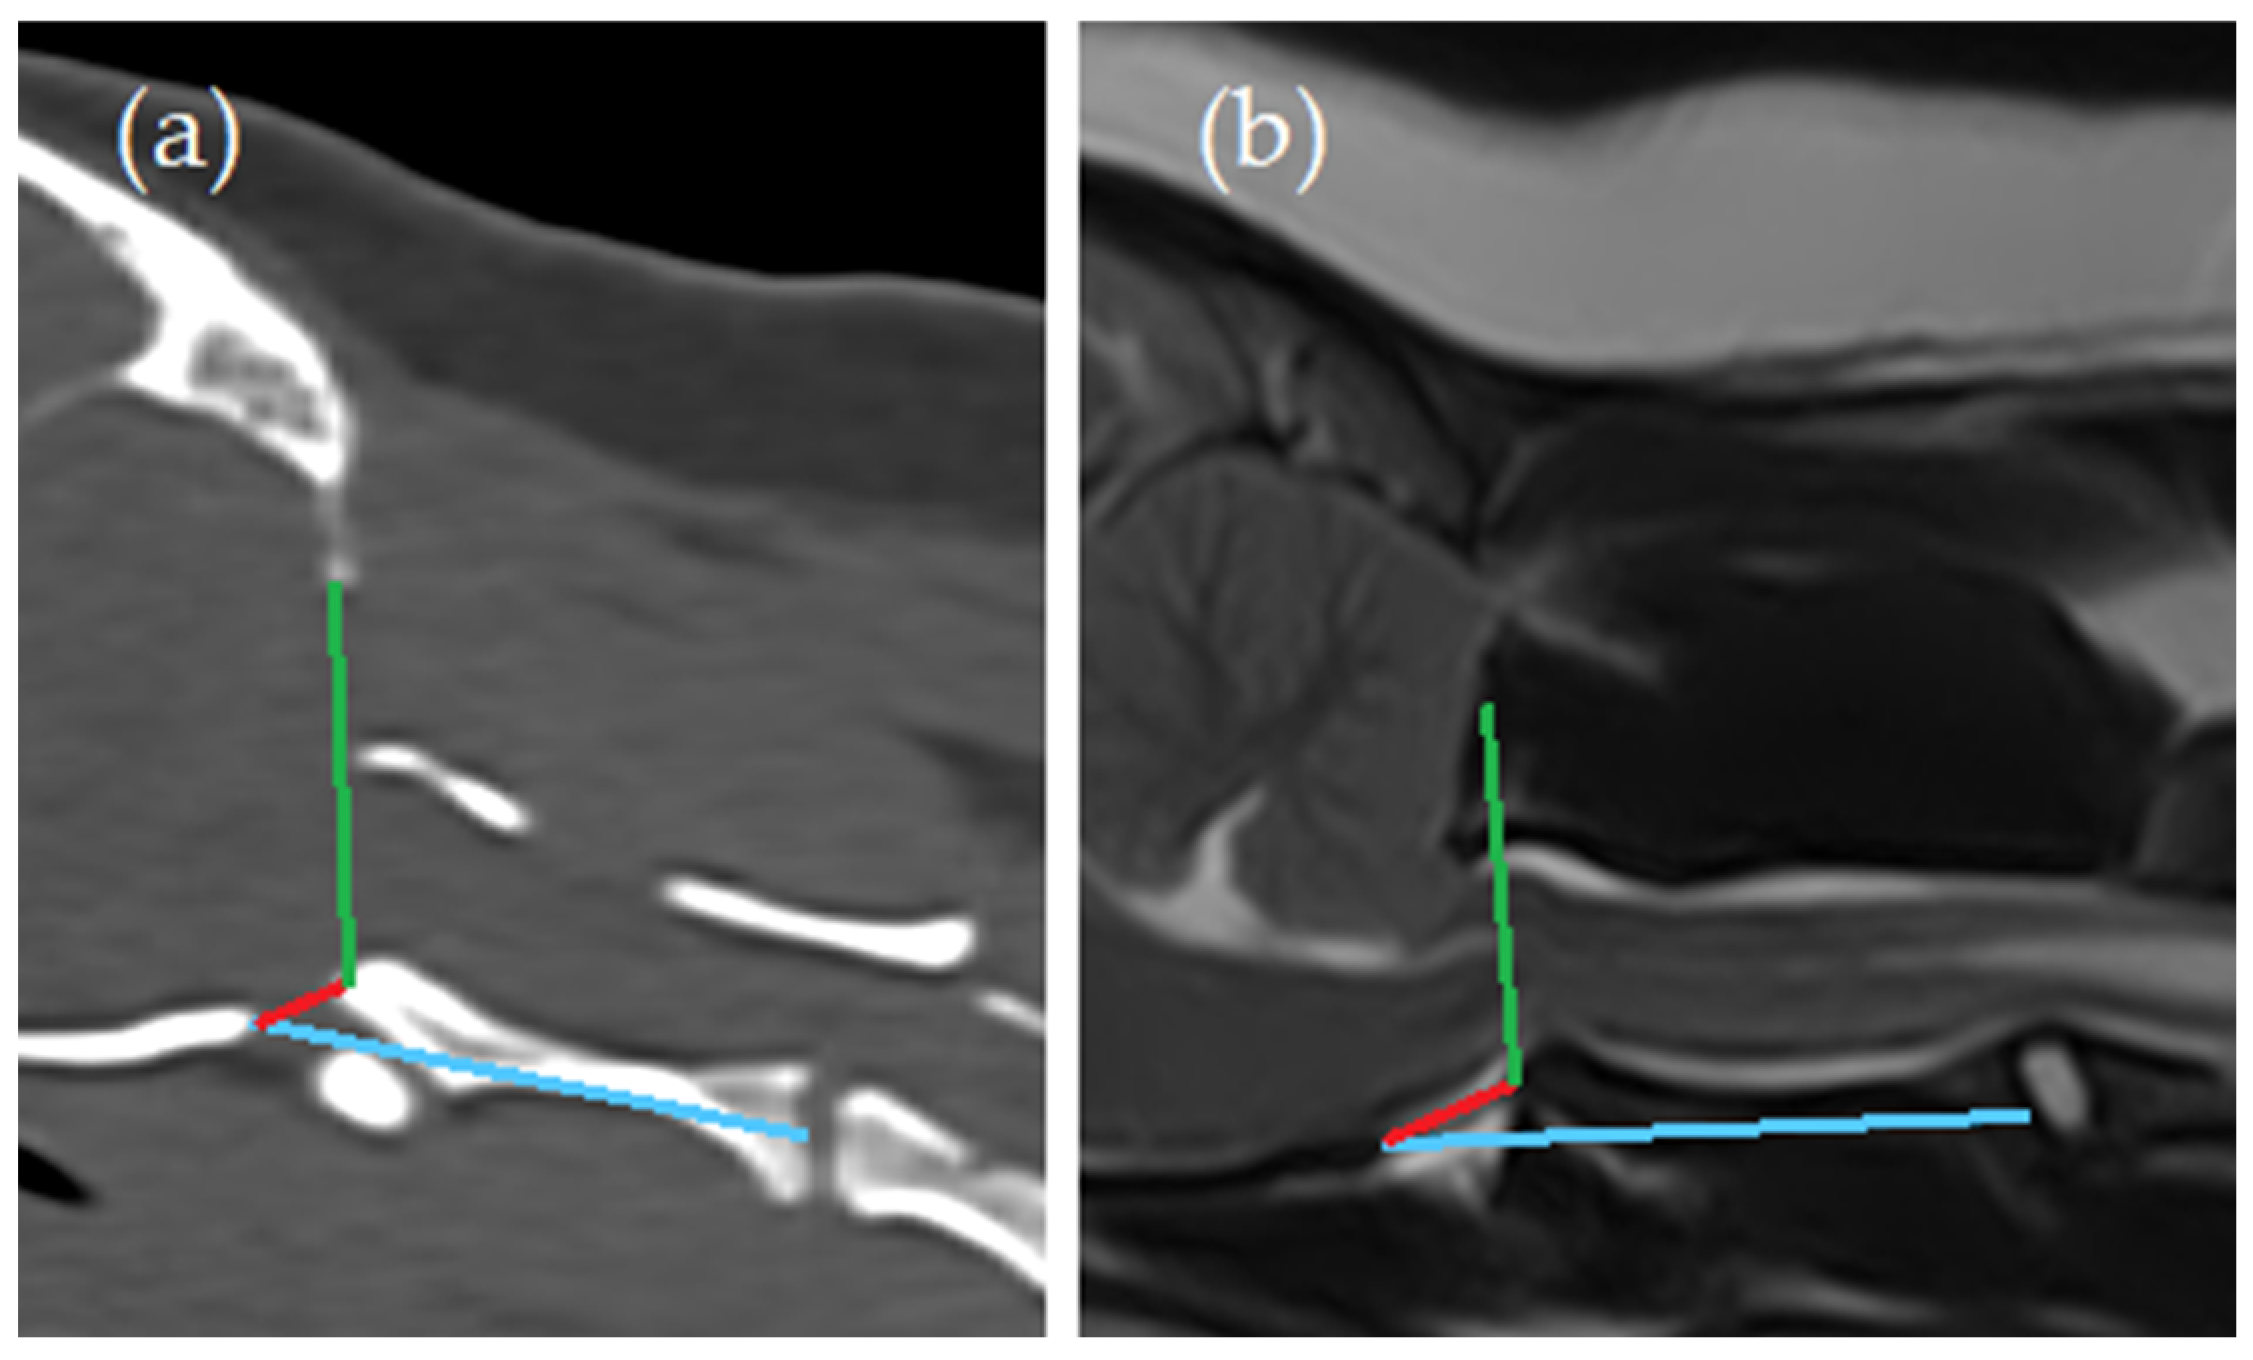

- Angle between the line from caudal tip of the basioccipital bone to the cranial tip of the dens axis (red line) and the line from the ventral aspect of the supraoccipital bone to the cranial tip of the dens axis (green line) (Angle 1);

- Angle between the line from caudal tip of the basioccipital bone to the cranial tip of the dens axis (red line) and the line from caudal tip of the basioccipital bone to the midpoint of the caudal endplate of the axis (blue line) (Angle 2).